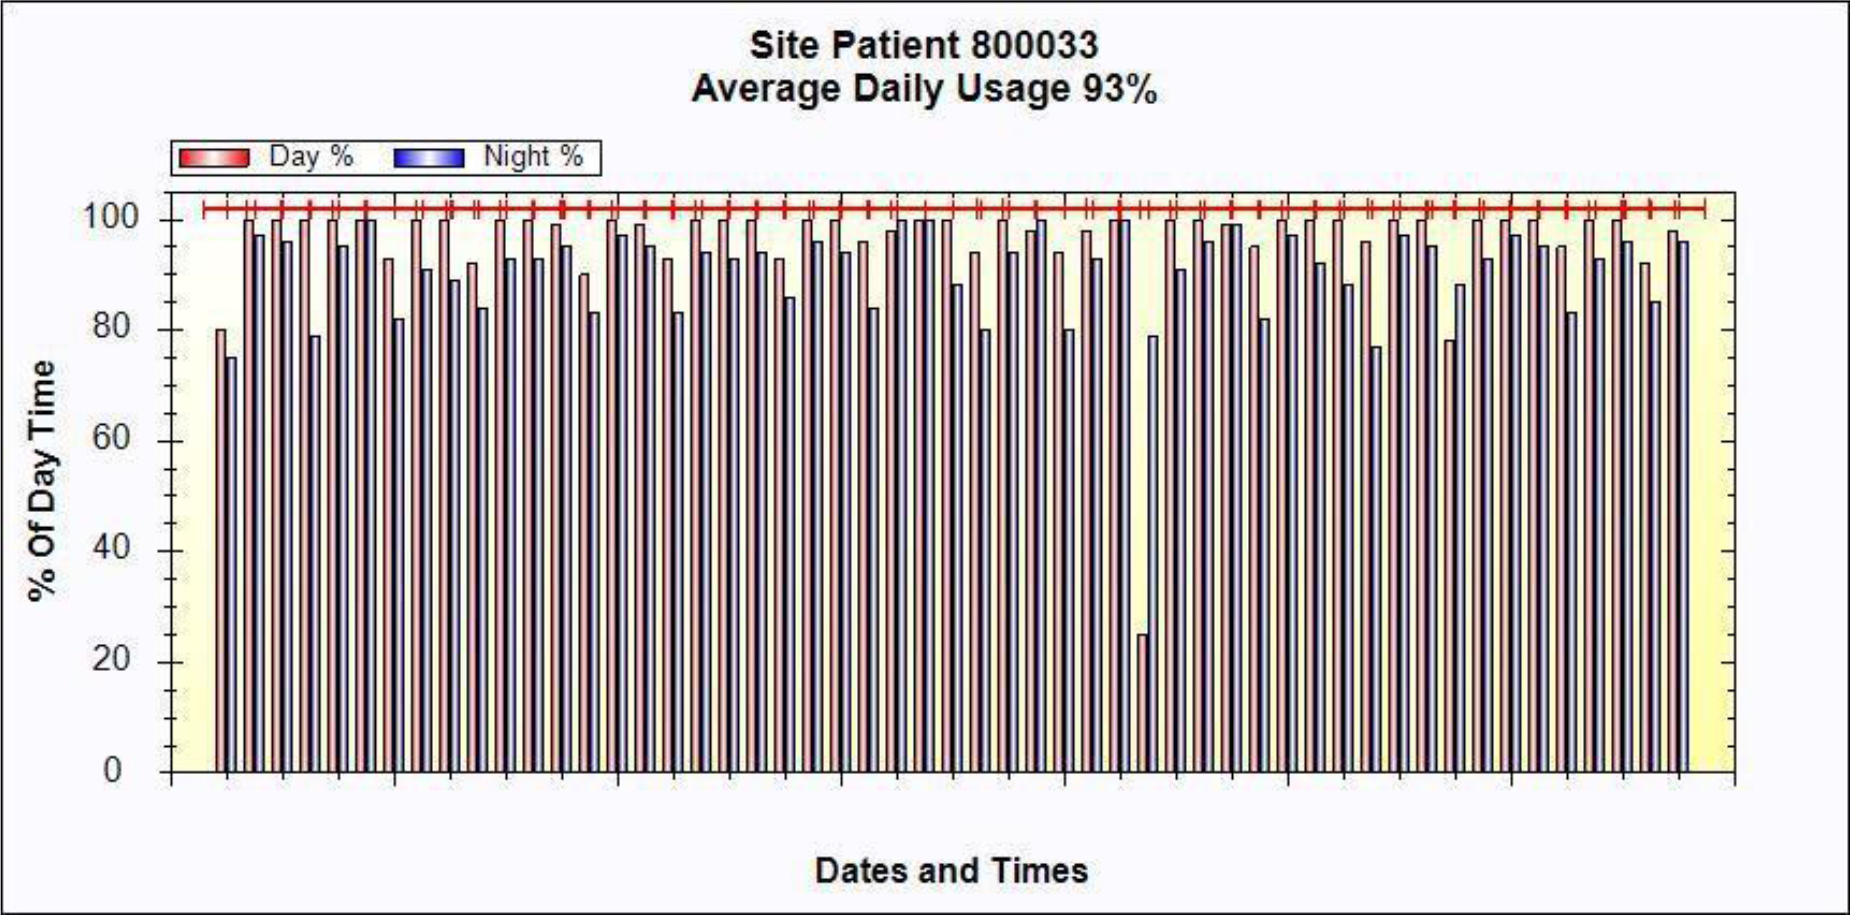

A 54-year-old female, developed a headache in December 2017. Examination showed that the left parietal occipital lobe occupied, and the first surgical treatment was performed, and the postoperative pathological diagnosis was glioblastoma. After operation, the patient received routine radiotherapy, 60Gy/33f, and temozolomide chemotherapy, 100mg/d (during radiotherapy), 300mg d1-5, q4w. In January 2019, the patient reexamined the MRI and found that the left temporal parietal space was occupied (Figure 1) and was operated again. The postoperative pathological diagnosis was still glioblastoma. The patient had occasional headache after operation, and the head MRI examination three months after operation indicated the progress of the disease (Figure 2). TTF was prepared to be used, and finally officially used the TTF treatment on July 4, 2019. The use time was relatively fixed, the utilization rate was 93%, and the compliance was good (Figure 3). During treatment, the patient developed allergic rash scattered on the scalp, mild itching, no ulceration and infection, and recovered quickly after topical application of antiallergic drugs. There had been several times that the patch temperature was too high, and the reasons are as follows: 1. The ambient temperature used was high (e. G. hot weather, direct sunlight, etc.). 2. The contact between the patch and the skin was not good. By instructing the patient to adjust the indoor temperature to about 24 °C, to use the headband or tape to strengthen the loose patch, to use the headband when sleeping at night, and to pay attention to clean the hair of the scalp every time, the situations had been significantly improved. Re-examination of the MRI in October 2019 showed that the condition was stable (Figure 4). Follow-up to 2020.1.23, the patient showed no symptoms of discomfort.

Figure 3